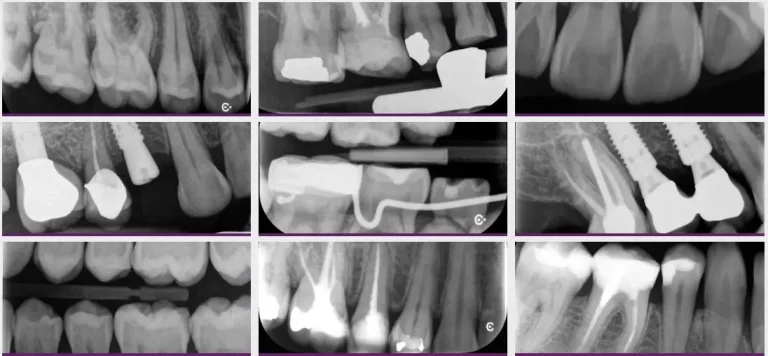

• La mejor calidad de imagen con una resolución real de hasta 17 pl/mm en tan solo 8 segundos para ver una imagen.

• Cubre la mayoría de las indicaciones intraorales, junto con exámenes periapicales, pediátricos y de aleta de mordida.